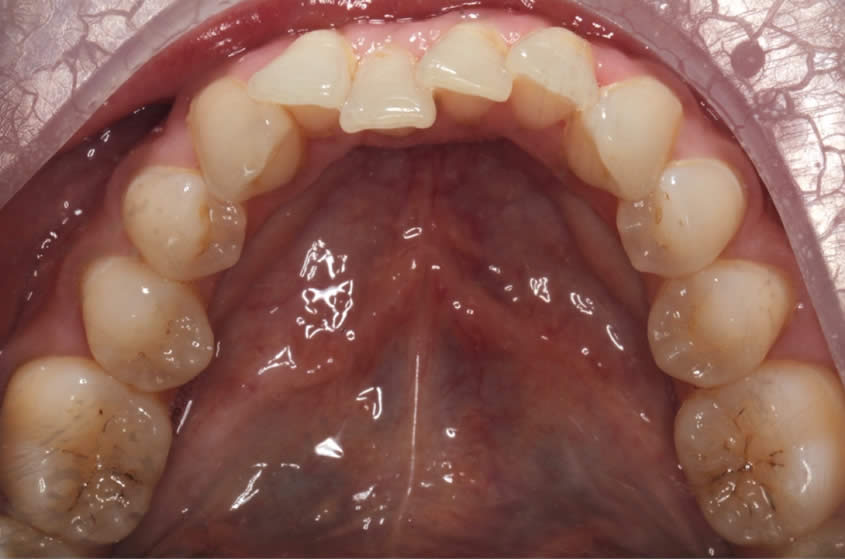

Patient Teeth Straightening Case

Teeth Straightening - Case 1